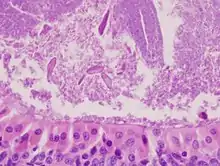

The appearance of this tumor under the microscope is unique. There are cystic spaces surrounded by two uniform rows of epithelial cells with centrally placed pyknotic nuclei. The cystic spaces have epithelium referred to as papillary infoldings that protrude into them. Additionally, the epithelium has lymphoid stroma with germinal center formation.

High magnification micrograph of a Warthin tumor showing the characteristic bilayered epithelium.